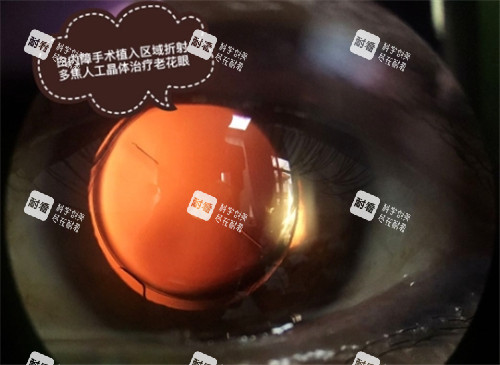

白内障手术一般采用超声乳化吸除联合人工晶状体植入术。

这是一种小创口手术,手术时间短,通常只需要 10 - 20 分钟。

手术过程中,医生会在患者的眼部做一个微小的切口,通过超声乳化仪将混浊的晶状体粉碎并吸出,然后植入人工晶状体。

整个手术过程患者一般处于清醒状态,但会使用局部麻醉,所以不会感到明显的疼痛。